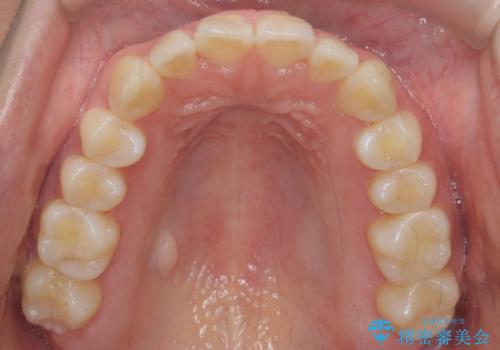

インビザライン モニター治療 前歯のねじれをまっすぐに

- 前歯のねじれを主訴に来院。

インビザラインの部分矯正コースではなく全体矯正コースをご希望でした。

前歯のねじれやがたつきだったため、モニター治療での低価格でのご提案が可能でした。

年齢が10代なこともあり、歯の動きは非常によく、リファインメントなしできれいに並びました。

下の前歯を少し削合して並べています。